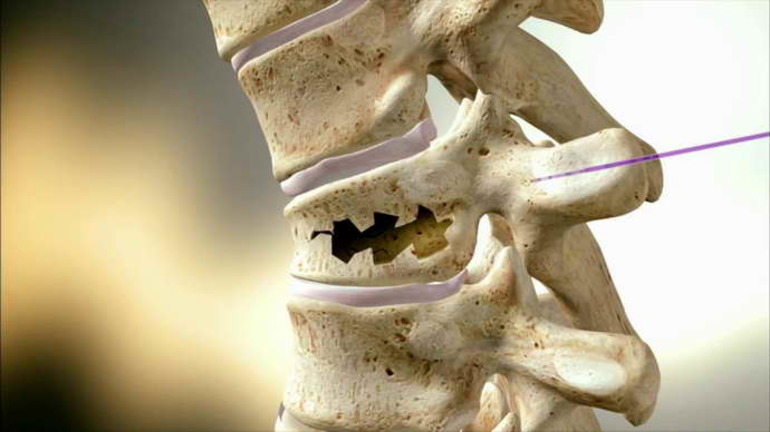

При синдроме Киммерли аномалия локализуется в области дуги С1. Образования представлены в виде тонкого мостика, при этом ограничивается пространство позвоночной артерии, нарушается кровоток и раздражается затылочный нерв. Существует 2 варианта аномалии:

Хирургическое вмешательство необходимо, если признаки синдрома не устраняются консервативными методами, пациента продолжают беспокоить обмороки, проблемы со слухом и зрением прогрессируют. Для проведения операции используются приборы оптического усиления.

Доступ осуществляется через маленький разрез в области атланта. Обнажается его задняя дуга, удаляется костный мостик. На оперированном участке артерии визуально различаются рубцы и сужения. Такие изменения подтверждают патогенетическую значимость синдрома. Если выявлены рубцы, их иссекает хирург во время операции.